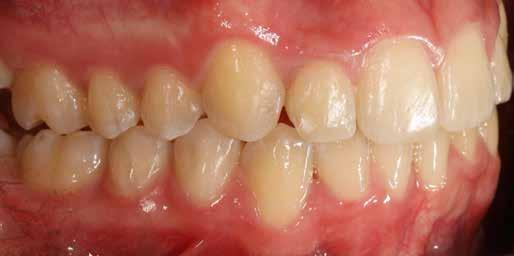

A fix fogszabályozó készülék mindössze 16 hónapos kezelés után került eltávolításra! Páciensünk legnagyobb örömére állcsontműtét nélkül sikerült mind az arcesztétikai, mind a funkcionális rehabilitáció (13–18. képek)